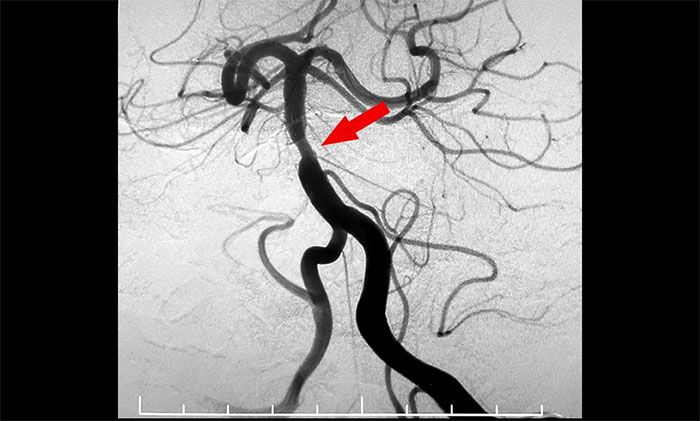

头颅MRI+SWI+DTI提示脑干梗塞,双侧桥臂变性;双侧放射冠区、额顶叶散在腔梗、缺血灶。基底动脉HRMR平扫+增强提示基底动脉管壁增厚伴重度狭窄。头颅CTP显示,右侧顶枕颞叶局部脑组织灌注较对侧稍减低。DSA提示基底动脉中段重度狭窄。

4A脑血管病一科主任席刚明教授,4A脑血管病一科副主任王贵平博士会诊指出,该患者为基底动脉主干病变,呈现为“一线天”样狭窄,考虑基底动脉重度狭窄为患者右侧肢体麻木并加重的根源。并且,狭窄处随时可能形成血栓引发血管急性闭塞,一旦闭塞,患者将可能出现深昏迷、四肢瘫痪,甚至危及生命,可以说“命悬一线”,即使侥幸保住性命,大概率也会成为植物状态或遗留其他严重残障。

▲ 基底动脉重度狭窄

▲ 基底动脉顺利开通